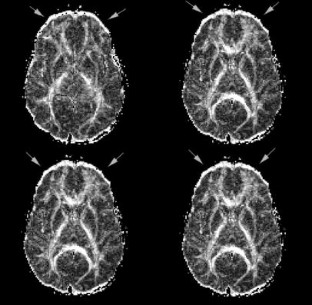

In all presented images (with exception of Fig. 1) full-tensor DWI was performed averaged over three data sets for a total acquisition time of 126 s. The entire diffusion tensor was sampled using a spin-echo single-shot echo-planar sequence repeated in six colinear directions. Imaging parameters were TR=6000 ms, TE=118 ms, slice thickness 6 mm, interslice gap 1 mm, field of view 40×20 cm, and acquisition matrix 256×128 pixels. Diffusion gradients were applied at a finite low b value (3 s/mm2) and a high b value (1221 s/mm2). The sequence has been previously described in detail [10]. In Fig. 1, images were averaged over eight data sets.